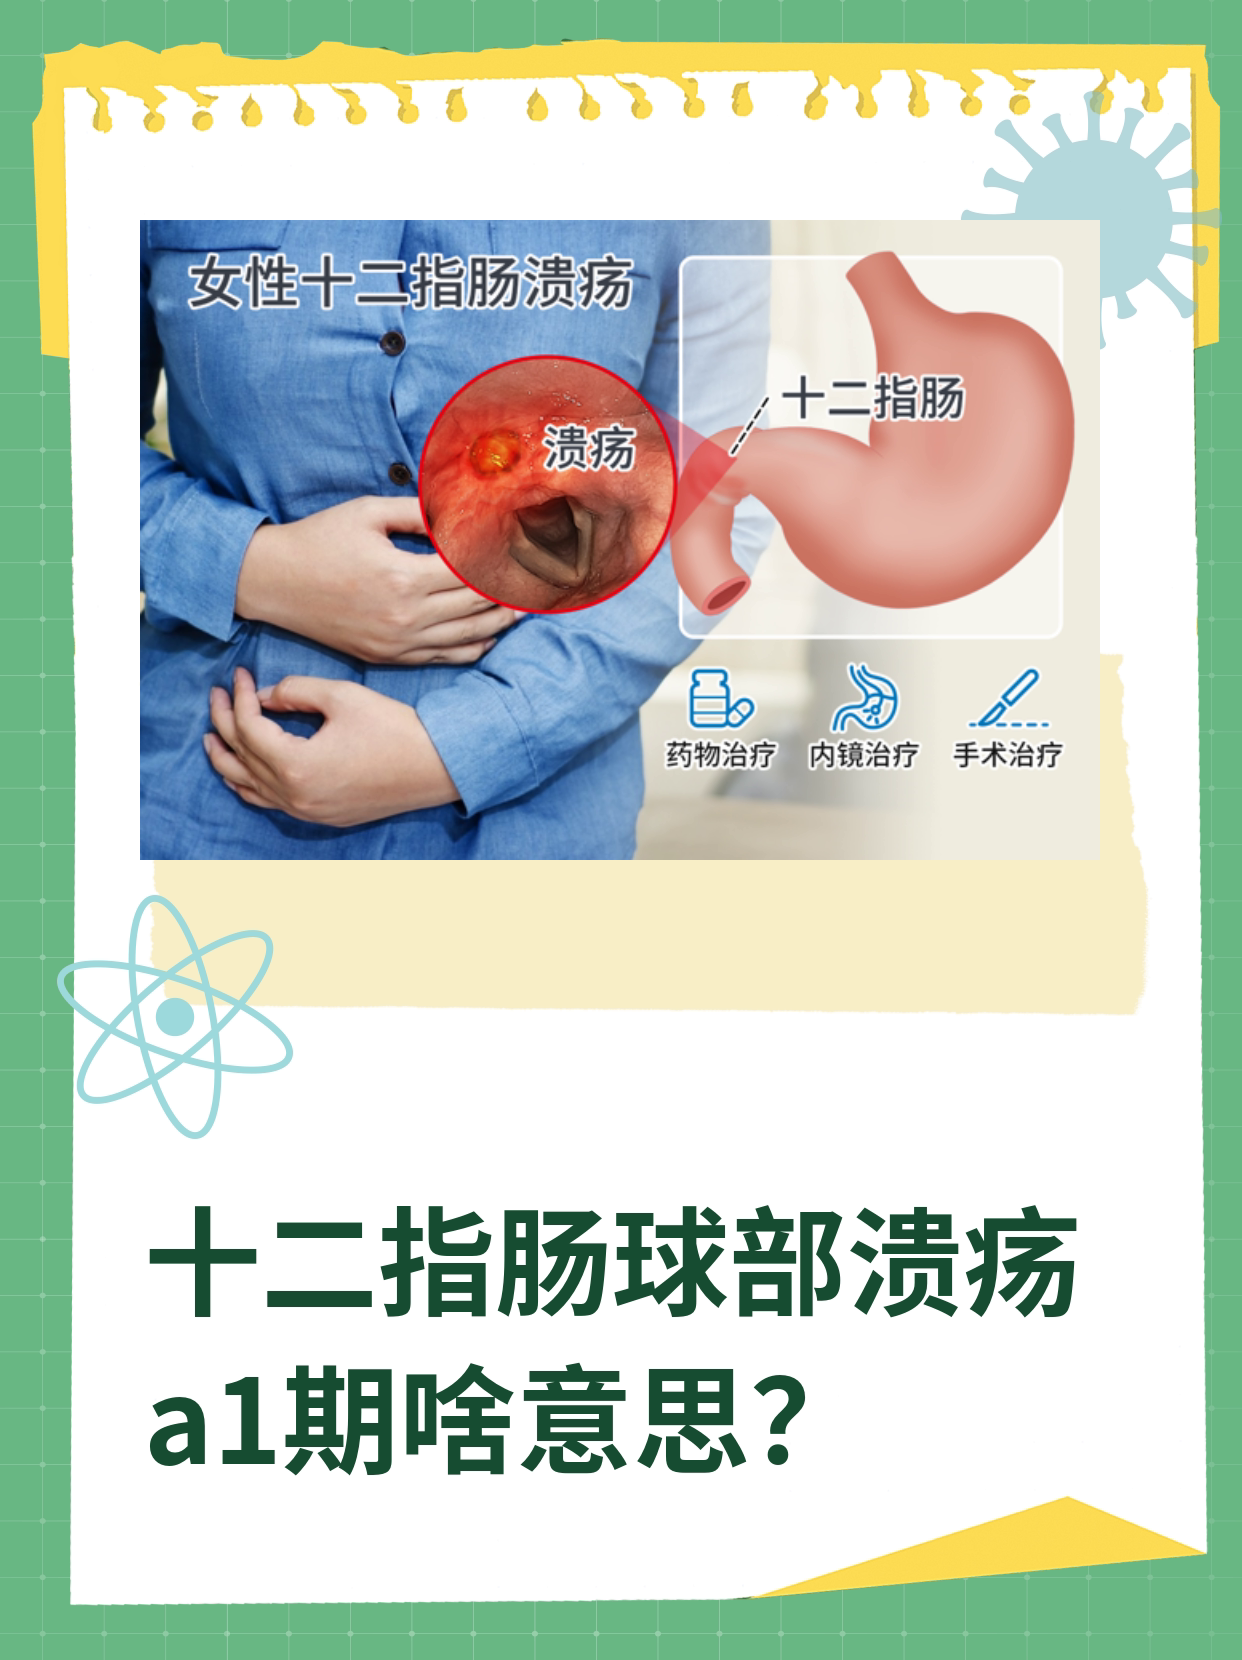

如发生一些急性全身性严重疾病,如大面积的脑梗脑出血心肌梗塞严重烫伤严重车祸多脏器损伤或严重的精神打击时,机体因为激素的特殊分泌,处于一个应激状态应激状态下胃酸分泌会增加,分泌明显增多,会导致胃肠道的应激性溃疡,不仅是食道胃,严重的还可出现在小肠,主要是胃和十二指肠球部。